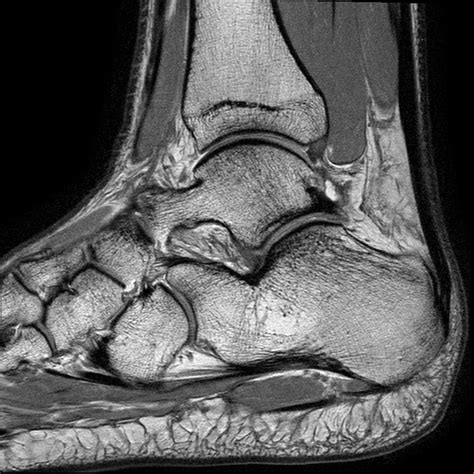

Soft Tissue Visibility

X-rays primarily show bones and are less effective at visualizing soft tissues. Conditions affecting muscles, tendons, and ligaments may not be fully apparent on an X-ray.

Soft Tissues

While X-rays primarily show bones, they can also provide some information about soft tissues. Any swelling, inflammation, or foreign objects would be noted.